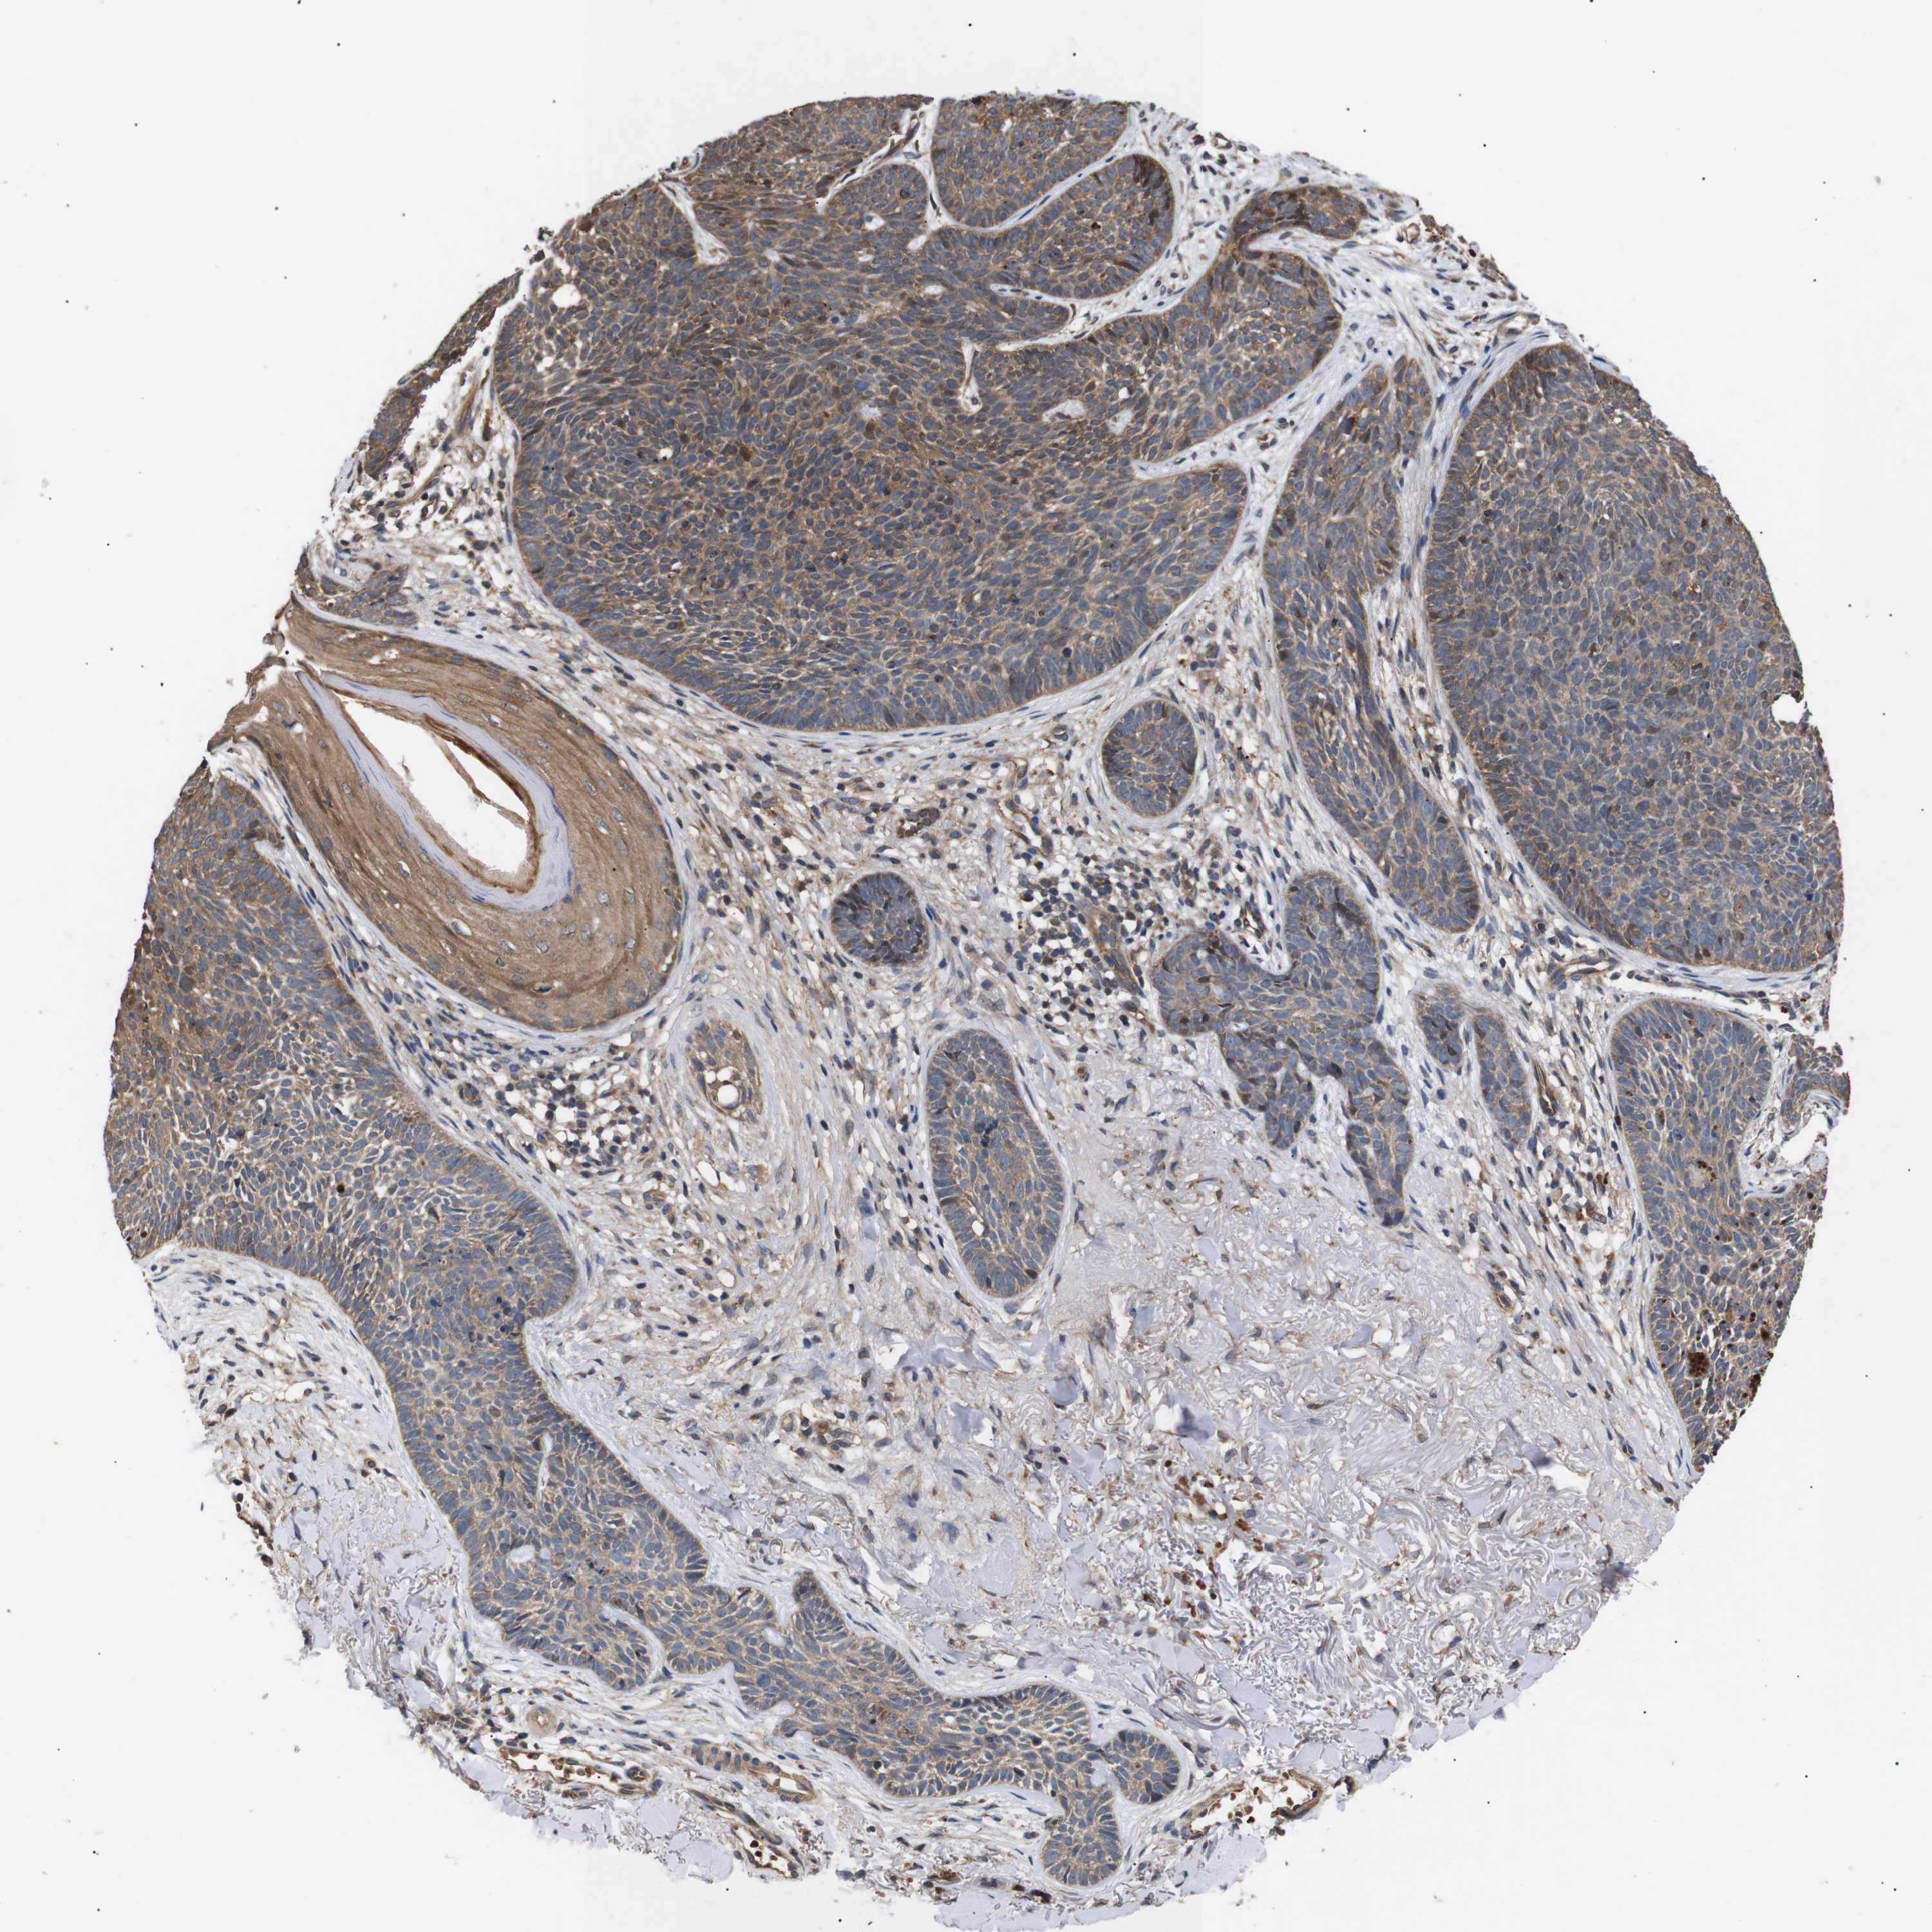

Basal cell and squamous cell cancer

SKIN CANCER - Protein expressioni

A mouse-over function shows sample information and annotation data. Click on an image to view it in a full screen mode. Samples can be filtered based on level of antibody staining by selecting one or several of the following categories: high, medium, low and not detected. The assay and annotation is described here.

Antibody stainingi

Antibody staining in the annotated cell types in the current human tissue is reported as not detected, low, medium, or high, based on conventional immunohistochemistry profiling in selected tissues. This score is based on the combination of the staining intensity and fraction of stained cells.

Each image is clickable and will lead to virtual microscopy that enables deeper exploration of all samples and also displays staining intensity scores, fraction scores and subcellular localization as well as patient and tissue information for each sample.

Antibody CAB010162

Antibody CAB025656

Staining

High

Medium

Low

Not detected

Intensity

Strong

Moderate

Weak

Negative

Quantity

>75%

75%-25%

<25%

None

Location

Nuclear

Cytoplasmic/membranous

Cytoplasmic/membranous,nuclear

Squamous cell carcinoma, NOS

Basal cell carcinoma

Squamous cell carcinoma, metastatic, NOS